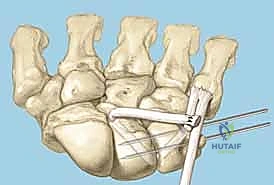

TECH FIG 6 • A. K-wire placed in triquetrum at a 45-degree angle.

TECH FIG 6 • B. K-wire advanced into lunate.

TECH FIG 6 • C. Second K-wire placed in lunotriquetral joint.

- K-Wire Placement: Once reduced, we need to temporarily stabilize the joint.

- First K-wire: Insert a 0.045-inch or 0.062-inch smooth K-wire into the triquetrum at approximately a 45-degree angle, aiming towards the lunate. Advance this wire across the lunotriquetral joint and into the lunate. Ensure good purchase in both bones.

- Second K-wire: Place a second K-wire across the lunotriquetral joint, ideally starting from the lunate and crossing into the triquetrum, or vice-versa, to provide rotational stability. This creates a more rigid construct.